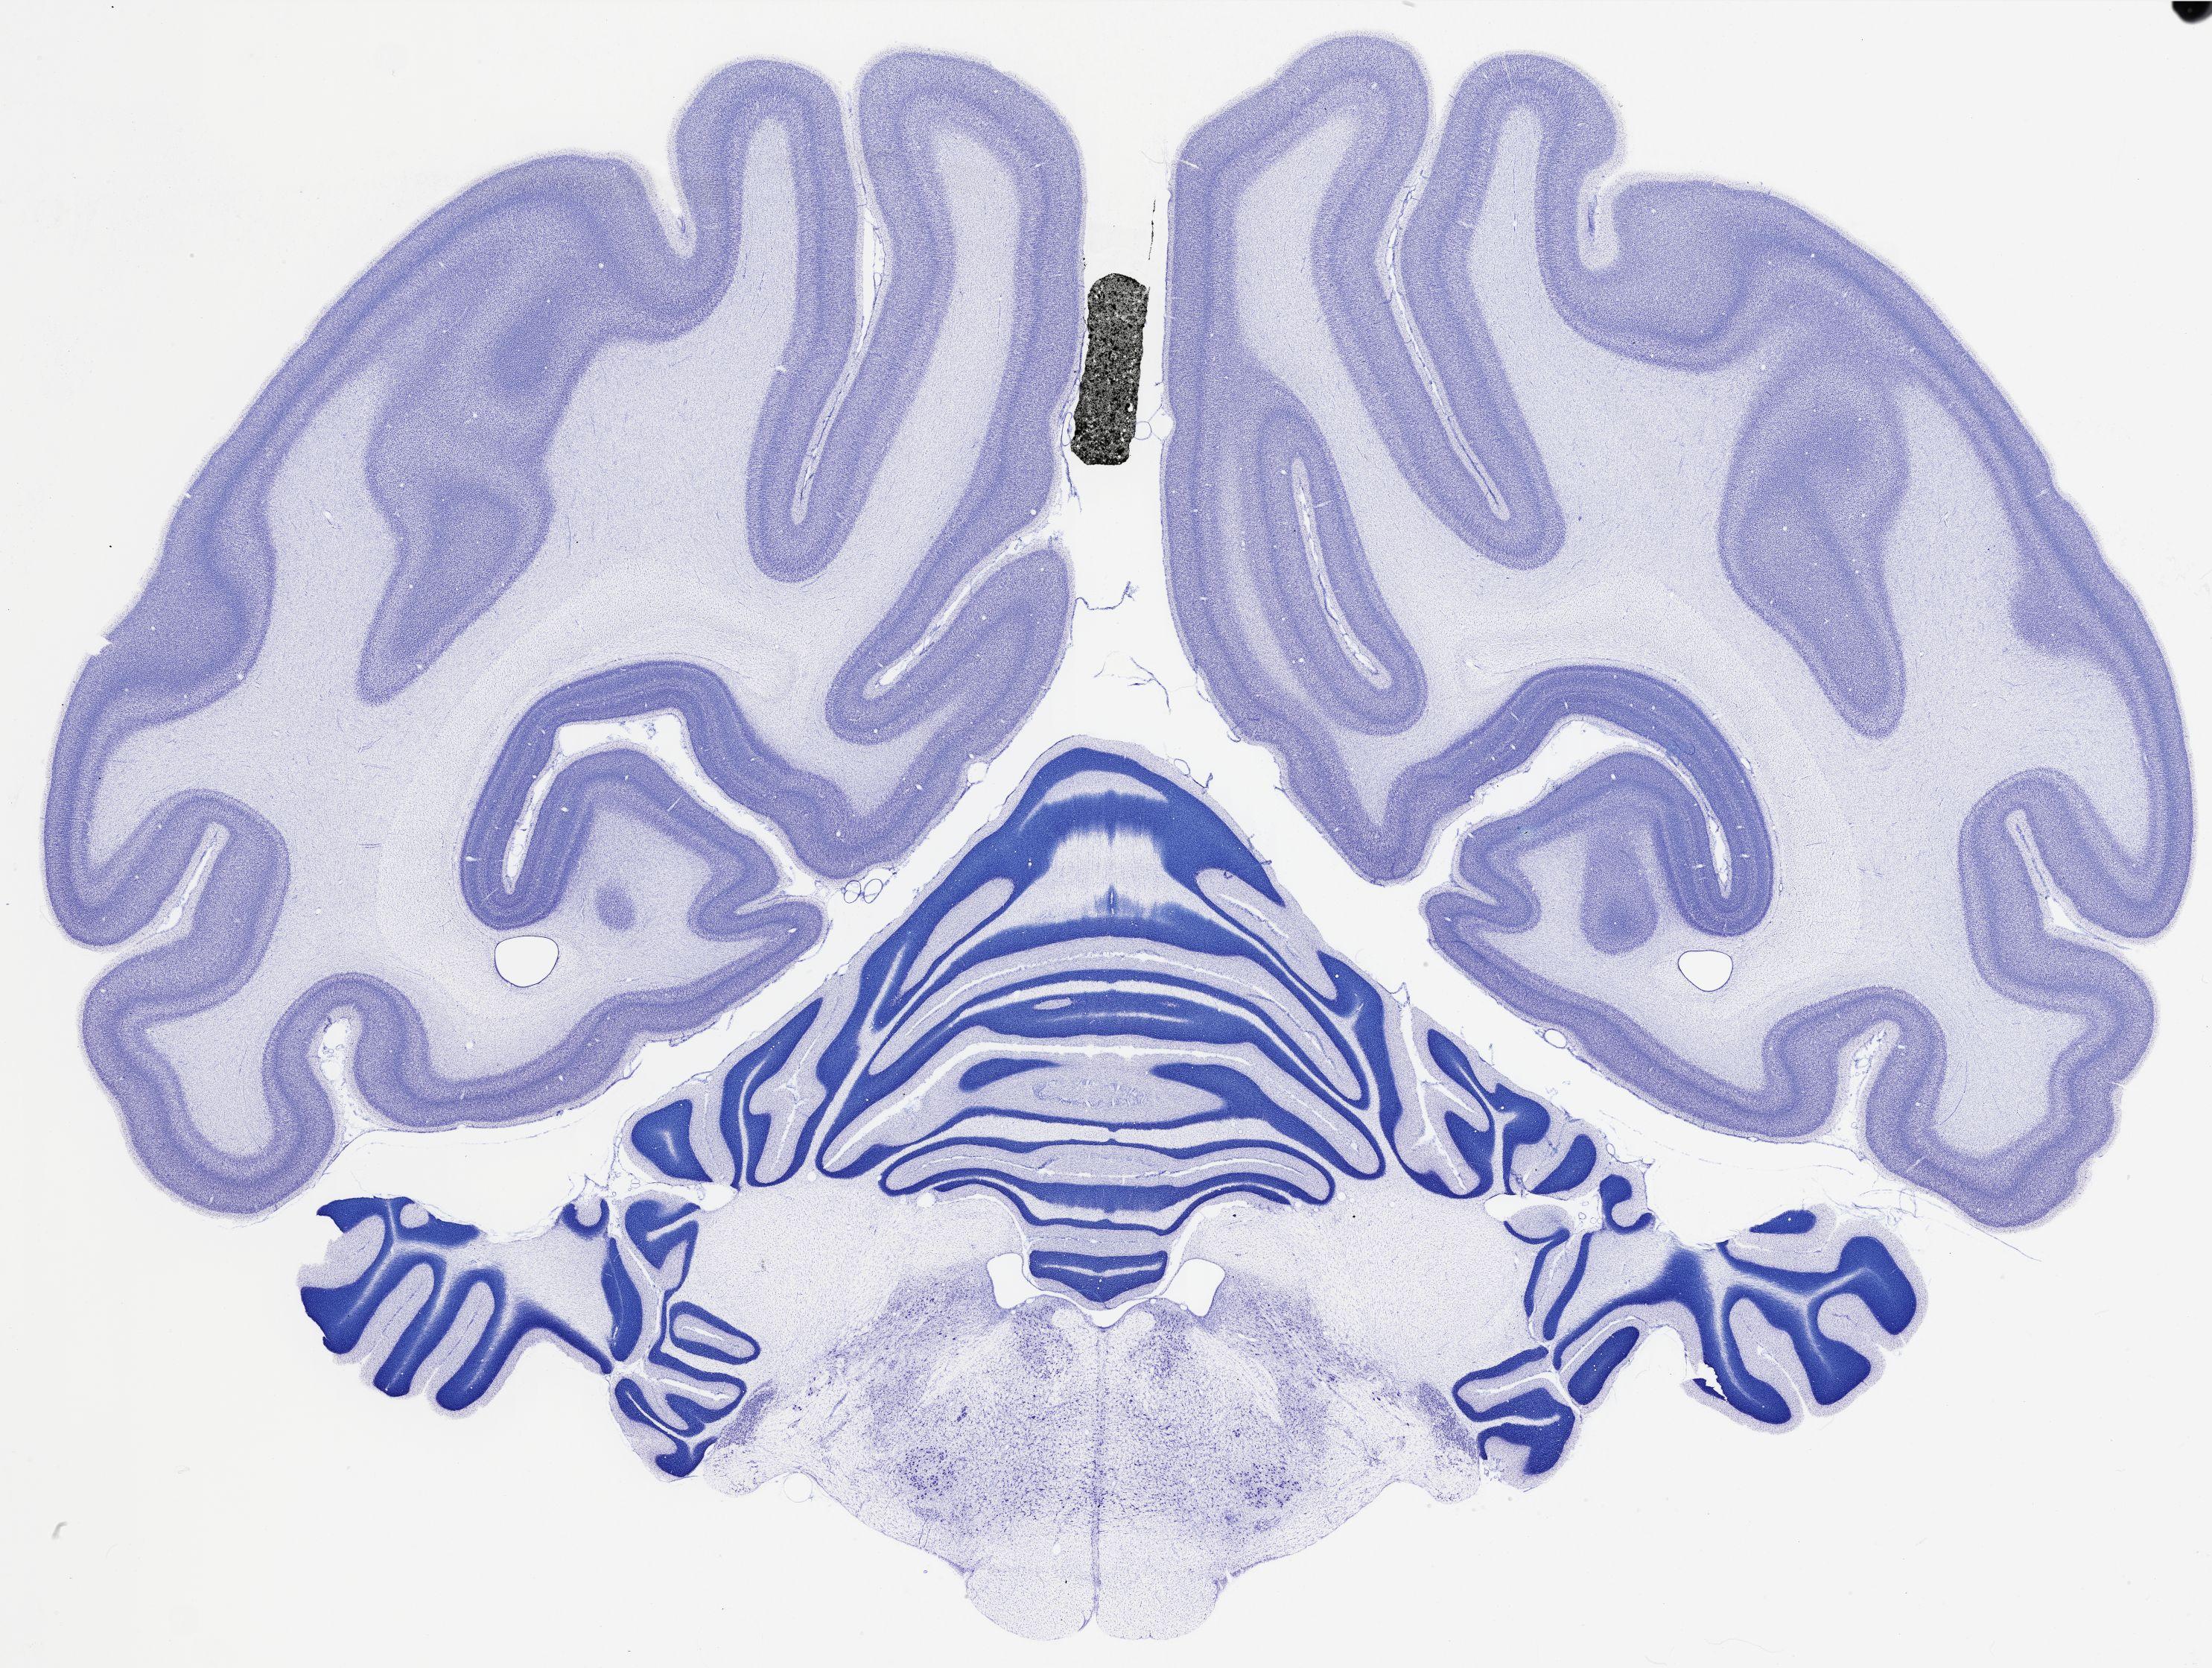

thumbnail

523